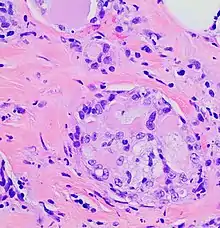

Histopathology of secretory carcinoma, high magnification. H&E stain. It characteristically shows nests of tumor surrounded by stroma, where the nests have microcystic and adenoid structures with eosinophilic secretions.

The microscopic histopathology of H&E-stained MSC tumors generally shows well-circumscribed solid tumors with multiple microcysts[13] and sheets of epithelial cells containing numerous vacuoles in their cytoplasm, signet ring cells (i.e. cells with one large cytoplasmic vacuole termed a globule), and extracellular droplet-like secretions resembling the cytoplasmic globules.[2] The sheets of cells are separated by bands of connective tissue.[5] In occasional cases, the cells in MSC tumors are arranged in a papillary (i.e. finger-like)[17] or tubular[14] pattern. The extracellular microcysts and intracellular vacuoles and globules stain red when stained with the H&E stain, consist of sulfated glycosaminoglycans and mucin-containing material,[4] and are identified using periodic acid-Shiff, PAD diastase, or Alician blue stains.[15] The term “secretory” for MSC is in recognition that the tumor cells vacuoles and globules are secreted extracellularly to give the tissues their microcystic appearance.[8] At least 2 cases of MSC had sarcoma-like malignant cells in portions of their tumors and a rapidly metastasizing disease.[18][19]